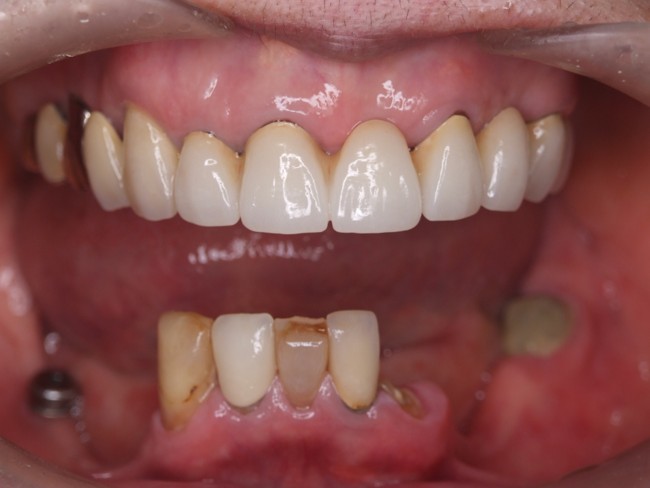

| 主訴 | 60代女性 他院で義歯を作ったが噛みにくい、バネを掛けている左下の銀歯が何度も取れる、しっかり噛めるようになりたい |

| 治療内容 | 歯周病組織再生療法、インプラント治療、セラミック治療を行いました。 |

| 治療費 | 4,000,000円(税込み) |

| 治療期間 | 1年半 |

| 治療回数 | 25回 |

| 想定されたリスク | 失活歯が多く、太くて長い土台がすでに入っていたので、歯根破折のリスクがあった |